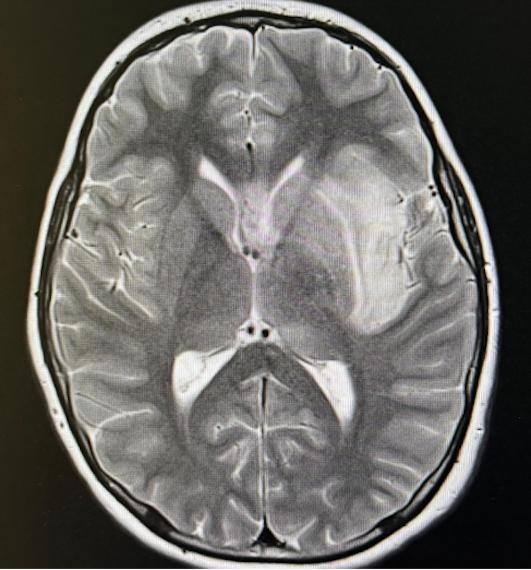

Alla rivalutazione emerge però un nuovo segno: un eloquio poco fluido. Il bimbo fatica a rispondere coerentemente anche alle domande più semplici, mostrando una difficoltà di produzione verbale, con una comprensione dei comandi preservata, e un disorientamento spazio-temporale. I genitori ci comunicano che in effetti anche il giorno precedente aveva alternato momenti di confusione a momenti di maggiore lucidità. Decidiamo quindi di eseguire l’emocoltura (che risulterà negativa), e valorizzando l’alterazione del sensorio e lo stato di vigilanza fluttuante, nel sospetto di encefalite, effettuiamo una rachicentesi. In attesa di liquor con PCR e colture, avviamo, a meno di 40 ore dall’inizio della sintomatologia, terapia endovenosa empirica con acyclovir, ceftriaxone e, successivamente, desametasone. Dopo circa 1 ora giunge l’esito chimico-fisico che mostra normoglicorrachia, lieve iperprotidorrachia e un aumento della cellularità (900/µl), a prevalenza mononucleata (> 90%). La PCR su liquor è dirimente: herpes simplex virus di tipo 1. Qualche ora dopo l’avvio della terapia ha avuto una crisi convulsiva focale e instabilità emodinamica per cui, previa esecuzione di TC (negativa), viene trasferito in rianimazione per monitoraggio intensivo e ottimizzazione della terapia. Nei giorni successivi l’EEG mostra anomalie epilettiformi tipiche a partenza temporale, e la RM un’alterazione di segnale in sede temporale (sx > dx) e spot microemorragici diffusi (Figura 1).

Durante i primi giorni di ricovero lo stato neurologico è fluttuante, ma con condizioni globali in lieve costante miglioramento. A circa 7 giorni dall’esordio la prognosi del nostro paziente si aggrava per un peggioramento dello stato neurologico, crisi ipertensiva (190/120 mmHg) e successiva anisocoria; effettua pertanto una TC che mostrerà un’infausta complicanza: un’emorragia cerebrale intraparenchimale massiva, in sede fronto-temporale sinistra (Figura 2).